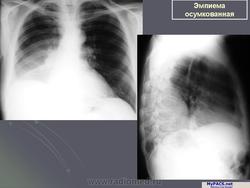

ОСУМКОВАННЫЕ ПЛЕВРИТЫ.

Выраженная тенденция плевральных листков к развитию слипчивого процесса объясняет значительную частоту возникновения осумкованных плевритов. Процесс осумкования, в значительной степени, зависит от образования шварт, которые формируются к концу первой недели патологического процесса.

На время формирования осумкованного плеврального выпота влияние оказывает также характер экссудата. Гнойный осумкованный выпот, как правило, прорывается в бронх или под кожу. Серозные и серозно-фибринозные осумкованные выпоты длительное время остаются без динамических изменений.

Наиболее часто осумковывается гнойный экссудат. Травматические геморрагические экссудаты также склонны к осумкованию.

Эмпиема плевры.

Гнойным плевритом или эмпиемой плевры называют скопление гнойного выпота в плевральной полости.

Эмпиема.